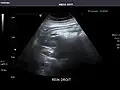

Right kidney